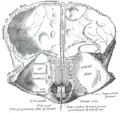

Левая теменная кость. В верхней части видны грануляции